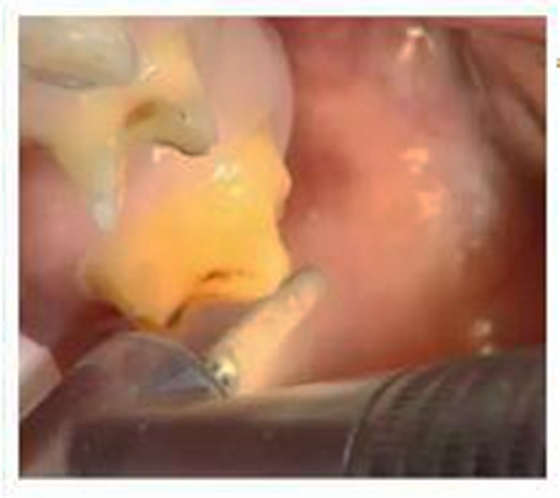

一、預(yù)備牙體

預(yù)備牙體常用車針:

備牙后需要使用沙粒較細(xì)的車針過順,使表面平溜,更易于修復(fù)體就位。